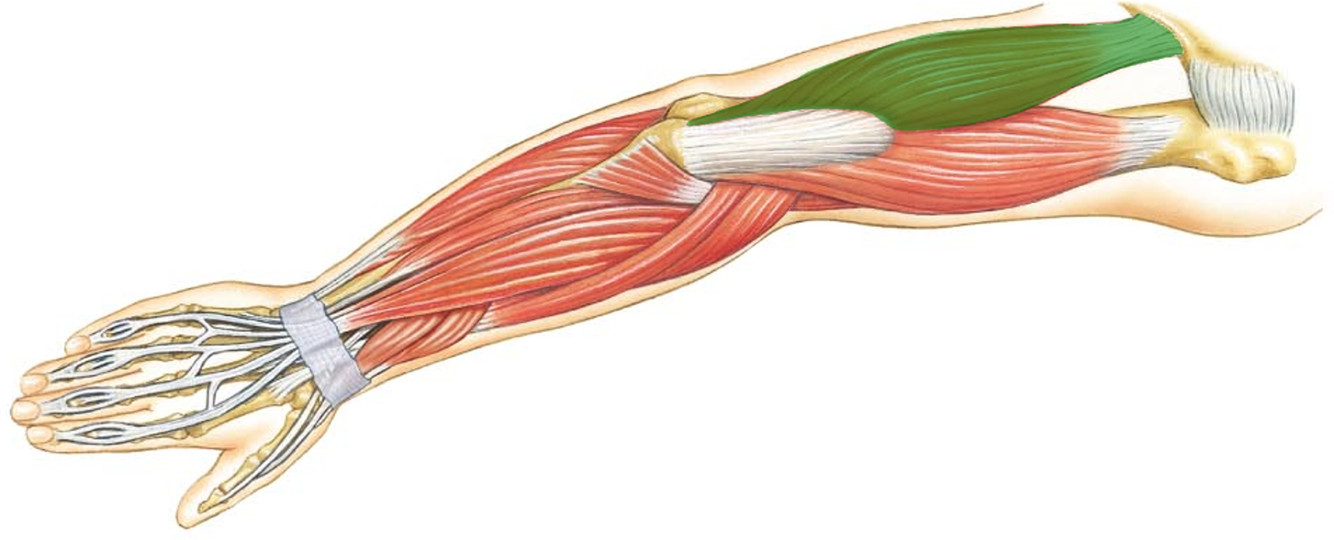

What is the innervation of this muscle?

Muscle - Flexor carpi radialis

Median nerve

What is the innervation of this muscle?

Muscle - Palmaris longus

Median nerve

What is the innervation of this muscle?

Muscle - Tibialis anterior

Deep fibular nerve

L4 + L5

What is the innervation of this muscle?

Muscle - Flexor digitorum superficialis

Median nerve

C7 - T1